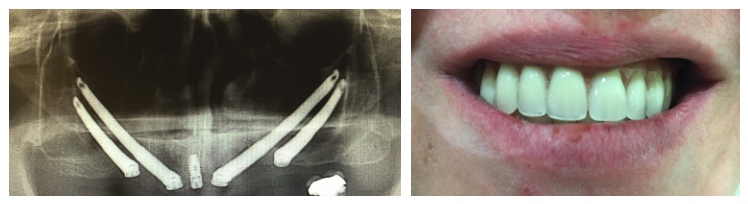

Paciente con atrofia maxilar total, resuelta con la colocación de 4 implantes zigomáticos. . La prótesis definitiva ha sido realizada en metal-cerámica.

Planificación informática y modelos 3D